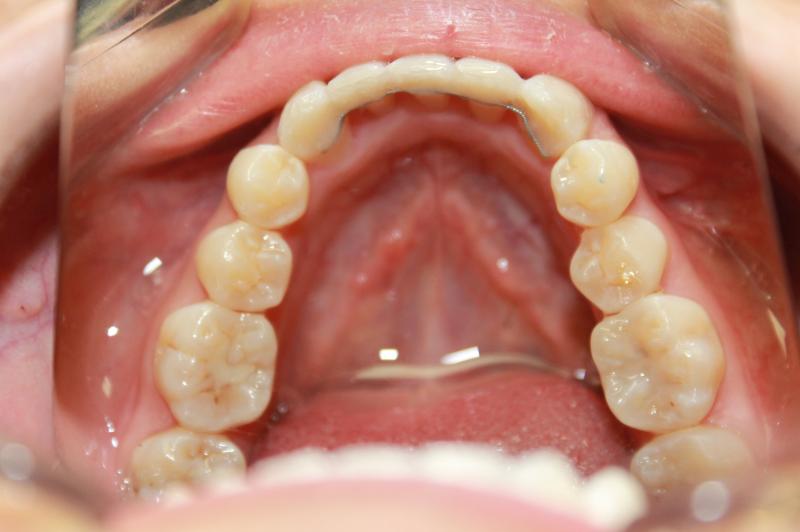

INVISALIGN - 13 months, 1 lower tooth removal, 1 series of aligners to align teeth and create the proper amount of space for 2 cantilever bridge to replace congenitally missing cuspids. COSMETIC DENTISTRY - 2 porcelain cantilever bridges and cosmetic bonding to reshape incisors and close gingival spaces. TOTAL TREATMENT TIME, 15 months

Cosmetic Dentistry, Mid-line Asymetry, Missing Teeth, Severe Crowding